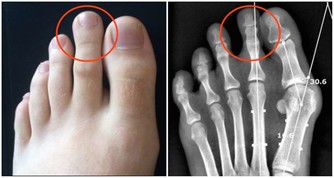

久之這些重金屬就會在腎小管內聚集,嚴重時甚至會引起腎小管的壞死。

但這個藥有個很大的毒副作用,就是損傷腎臟,像氨基糖甙類抗生素一樣,引起腎小管壞死。

我們吃下去之後,這些重金屬就會沉積在我們的腎小管內,久而久之,就會傷及我們的腎臟。

一旦我們再有個高血壓、糖尿病什麼的毛病,腎臟的代償能力會進一步下降。